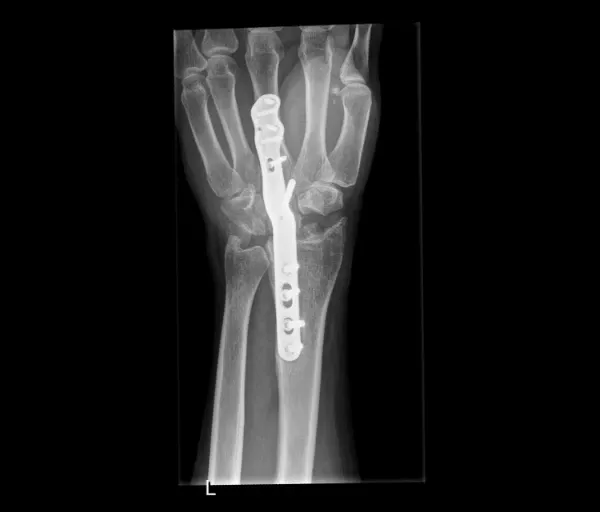

Indien de breuk verplaatst is of onvoldoende stabiel:

- Pinnen (Kapandji-techniek): metalen pinnetjes door de huid, blijven 6 weken; risico op lichte inzakking

- Plaat en schroeven: meest gebruikte techniek; geeft meer stabiliteit en kortere gipsperiode; plaatje hoeft meestal niet verwijderd te worden

- Externe fixator: uitwendig frame, gebruikt bij open breuken